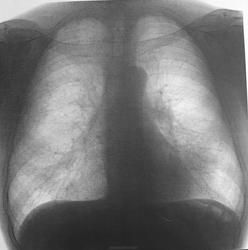

Больной 63, крановщик, курильщик. Перенес левостороннюю пневмонию 15.12.2010 (рис.1). В течение 10 дней до рентгенографии грудной клетки от 1.4.2011 (рис.2.3.4) беспокоит сухой кашель. Температура тела нормальная. С уважением Nikolas

Согласен с doktor-rentgen. По этой же причине повышена прозрачность лев. лёгкого. Изображения в целом вызывают уныние, особенно первое: слишком много информации потеряно. Но нельзя отрицать уменьшения объёма в/доли пр. лёгкого. Без томографии не обойтись.